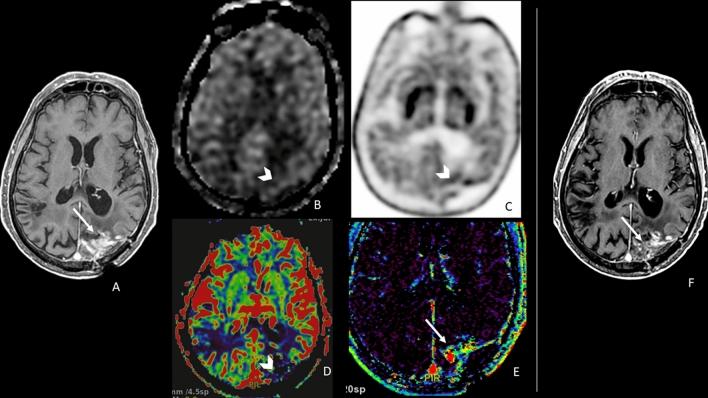

To discriminate between post-treatment changes and tumor recurrence in patients affected by glioma undergoing surgery and chemoradiation with a new enhancing lesion is challenging. We aimed to evaluate the role of ASL, DSC, DCE perfusion MRI, and 18F-DOPA PET/CT in distinguishing tumor recurrence from post-treatment changes in patients with glioma.

We prospectively enrolled patients with treated glioma (surgery plus chemoradiation) and a new enhancing lesion doubtful for recurrence or post-treatment changes. Each patient underwent a 1.5T MRI examination, including ASL, DSC, and DCE PWI, and an F-DOPA PET/CT examination. For each lesion, we measured ASL-derived CBF and normalized CBF, DSC-derived rCBV, DCE-derived Ktrans, Vp, Ve, Kep, and PET/CT-derived SUV maximum. Clinical and radiological follow-up determined the diagnosis of tumor recurrence or post-treatment changes.

We evaluated 29 lesions (5 low-grade gliomas and 24 high-grade gliomas); 14 were malignancies, and 15 were post-treatment changes. CBF ASL, nCBF ASL, rCBV DSC, and PET SUVmax were associated with tumor recurrence from post-treatment changes in patients with glioma through an univariable logistic regression. Whereas the multivariable logistic regression results showed only nCBF ASL (p = 0.008) was associated with tumor recurrence from post-treatment changes in patients with glioma with OR = 22.85, CI95%: (2.28-228.77).

In our study, ASL was the best technique, among the other two MRI PWI and the 18F-DOPA PET/CT PET, in distinguishing disease recurrence from post-treatment changes in treated glioma.